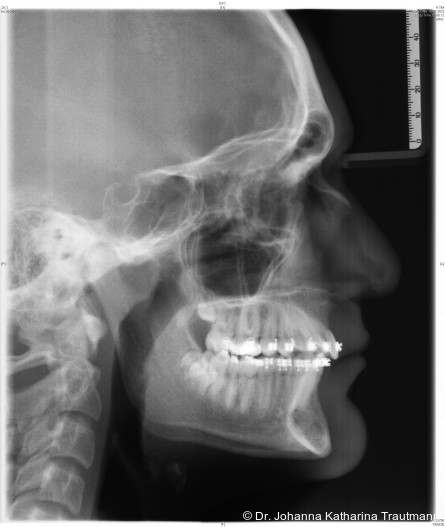

Das Fernröntgenseitenbild zeigte eine skelettale Klasse IIAnomalie mit einem Wits von 5,6 mm, bei einer tiefen Konfiguration (ML NL = 16,5°) mit bialveolär retrudierten Fronten (OK1NA = 5,9°; UK1NB = 10,4°), was sich auch in der Modellanalyse widerspiegelte. Hier zeigte sich zudem ein schmaler Oberkiefer mit multiplen Kippungen und Rotationen in der Front, einem hypoplastischem 22 sowie einer Mesialwanderung des 16. Des Weiteren zeigte sich eine asymmetrische Bisslage mit 1 PB distal rechts und ½ PB distal links bei einem Overjet von 2,5 mm sowie einem Overbite von 5 mm. Während im Unterkiefer bereits die zweite Zahnwechsel phase begonnen hatte, zeigte sich im Oberkiefer noch kein Wechsel in den Stützzonen. Gerade bei Patienten mit Spaltbildungen ist eine engmaschige Überwachung des Durchbruchs der oberen Eckzähne essenziell. Während bei der Allgemeinbevölkerung die Prävalenz von verlagerten Eckzähnen bei ca. 2,8 Prozent liegt2, ist diese bei Patienten mit Lippen-Kiefer-Gaumen-Spalten um den Faktor 10 erhöht.3, 4 Als klassische Risikofaktoren gelten zudem Platzmangel, transversale Enge aber auch Fehlstellungen, Nichtanlagen oder Hypoplasien der zweiten Schneidezähne. Diese übernehmen normalerweise die Funktion der Leitschiene für den S-förmigen Durchbruch der Eckzähne. Im vorliegenden Patientenfall kommen also mehrere Risikofaktoren für eine Verlagerung zusammen, was die rechtzeitige Diagnostik zur Abklärung einer Durchbruchsproblematik rechtfertigt. Da im Spaltbereich auch zusätzlich ein ausgeprägtes Knochendefizit vorliegen könnte, sollte auch immer die Option einer sekundären Osteoplastik abgewogen werden, deren Indikation und Timing optimal zum Durchbruch der Canini angepasst werden sollte.5